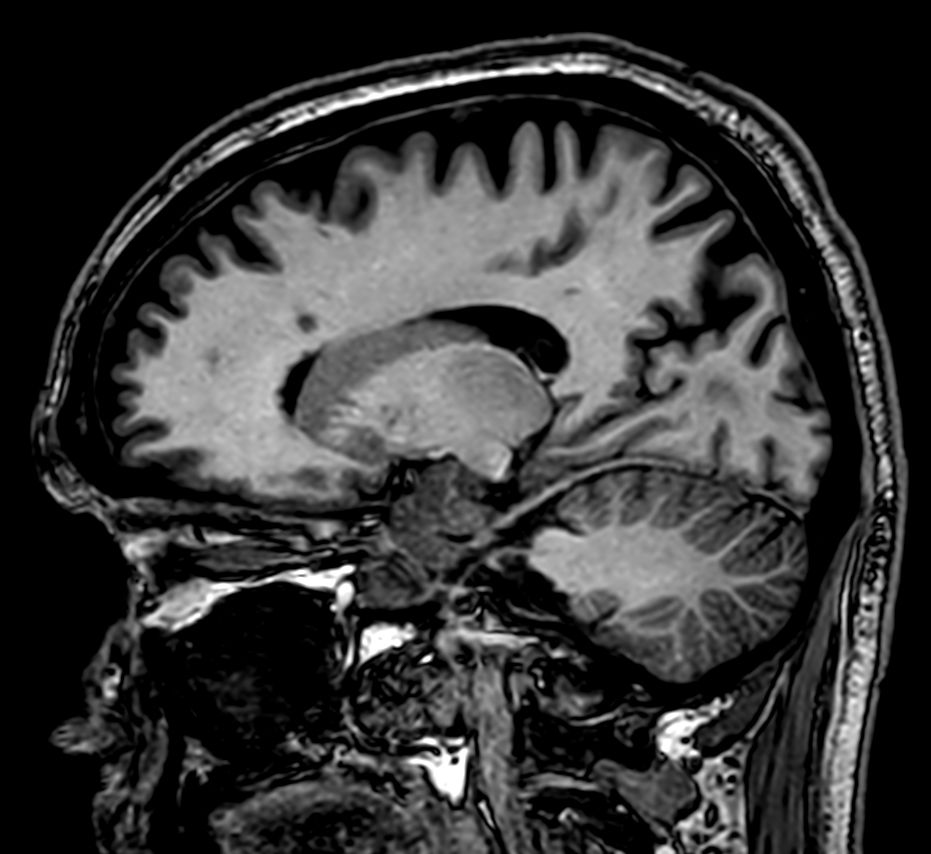

T2w TSE MultiVane XD